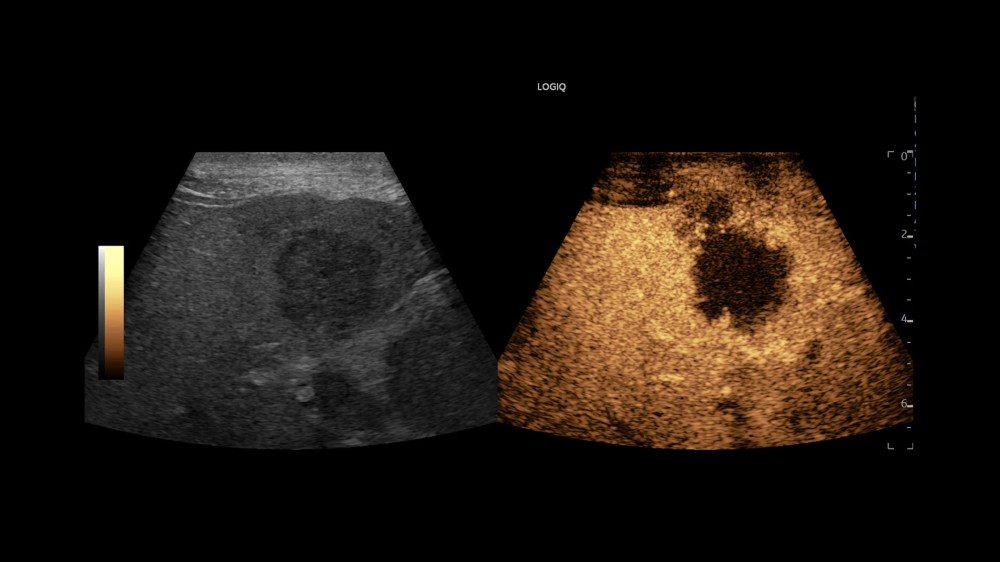

MVI (Micro Vascular Imaging): Kiçik damarların yüksək dəqiqlikli qiymətləndirilməsini təmin edən mikro-damar görüntüləmə rejimi.

Radiantflow™: Kiçik damarların üçölçülü vizuallaşdırılmasını təmin edən texnologiya, MVI ilə birlikdə istifadə edildikdə damar morfologiyasının təhlilini asanlaşdırır.